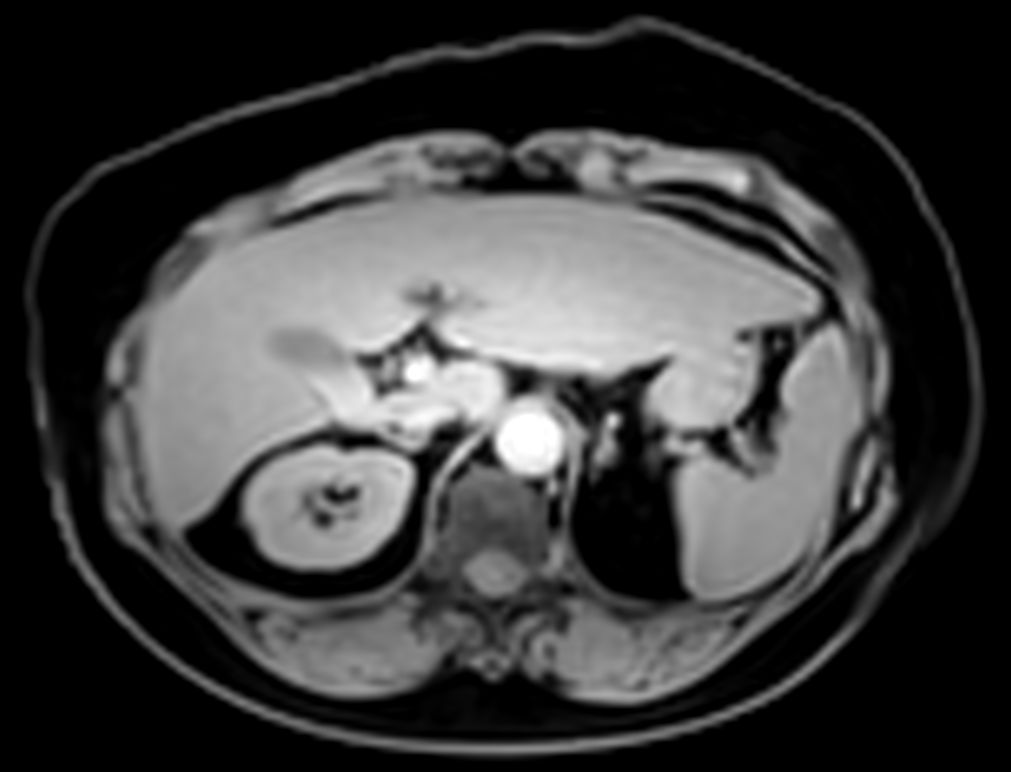

MR Elastography (SE-EPI, 4 slices) (Stiffness Map)

MR Elastography (SE-EPI, 4 slices) (processing)

Liver ExamCard including single breath hold 3D mDIXON Quant for non-invasive liver fat quantification of the whole liver with high accuracy (± 3.5%) and reproducibility (± 1.4%)1. And MR Elastography for a non-invasive assessment of differences in tissue stiffness of the liver. Image processing is fully integrated at the scanner with automated calculation of Elastograms, reflecting tissue stiffness in kPa and statistical confidence map for reliability assessment.